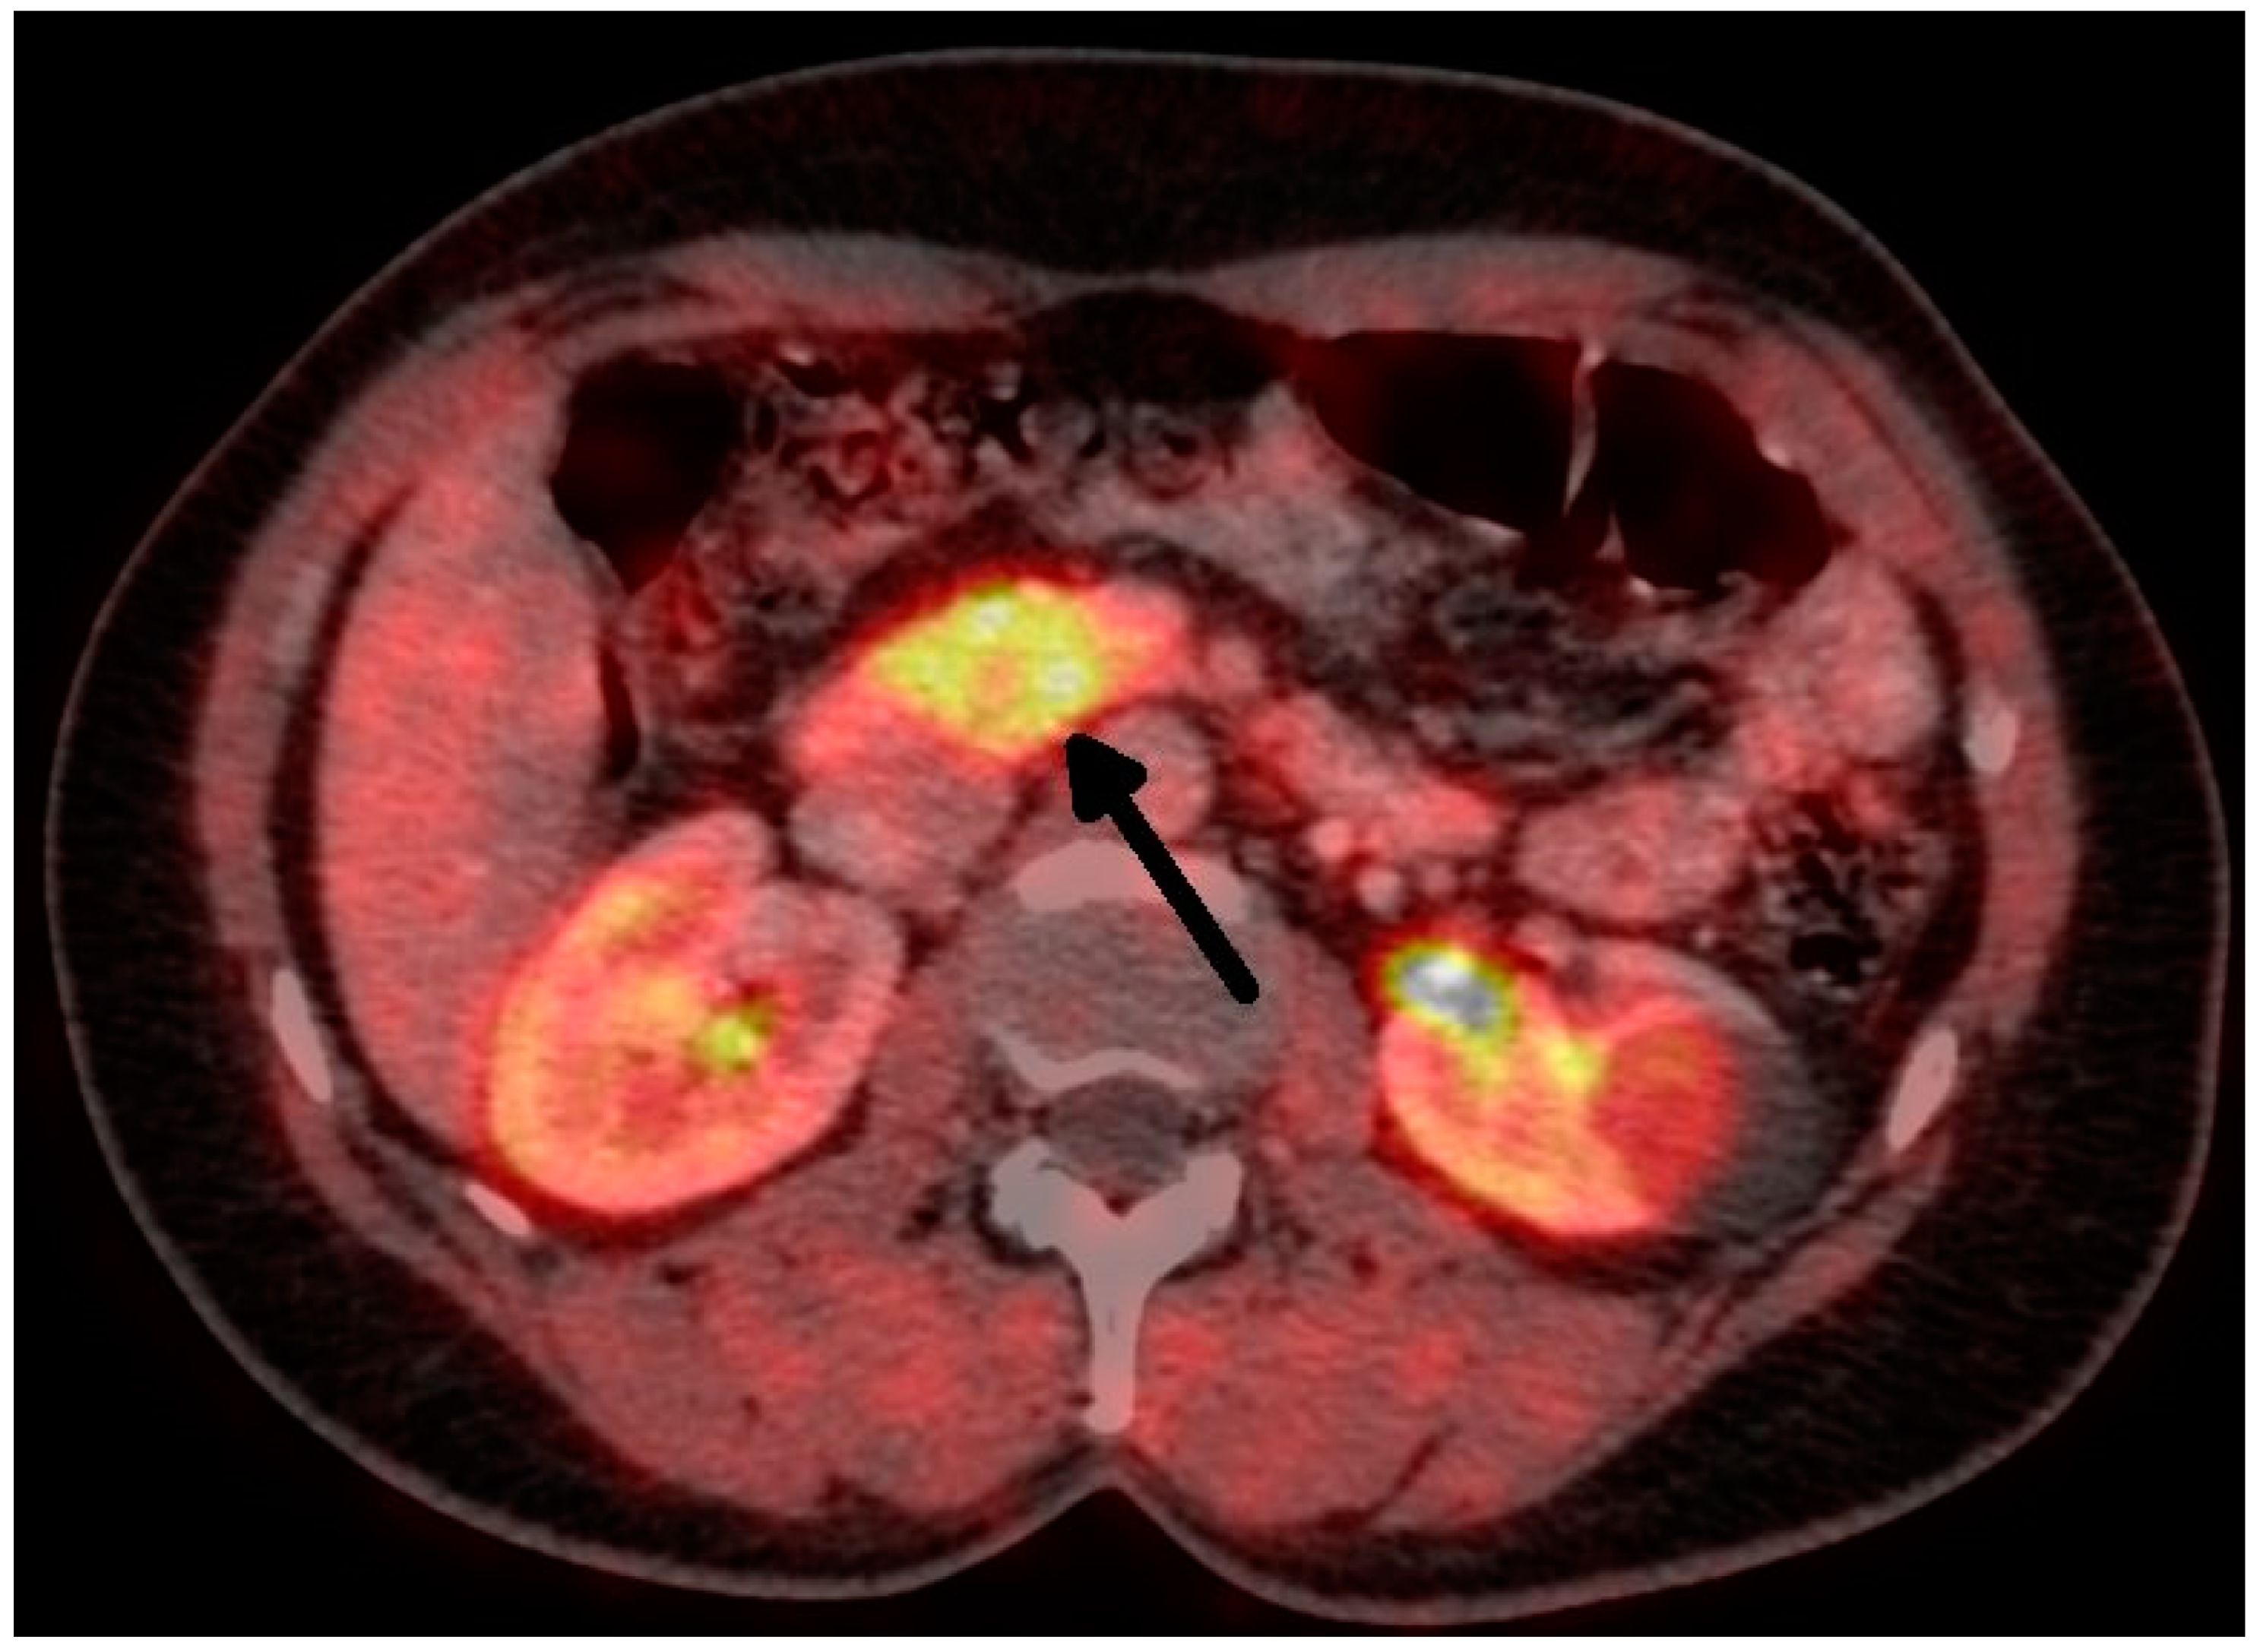

The treatment of choice is surgery. Therefore, it is necessary to establish the precise localization of the tumor. The sensitivity and specificity of radiodiagnostic methods are rising. A conventional CT scan has a sensitivity of about 33%, while that of a single-slice helical CT is 58%, and that of multidetector CT is 75–100% [8]. Insulinomas are hypervascular, so they have greater enhancement during the arterial phase of the examination. The can be said of MRI. A conventional MRI can detect insulinoma in about 31% of cases, and multiphasic MRI can detect insulinoma in 85% of patients [4]. The use of 18 F-fluorodeoxyglucose (18 F-FDG) PET is not helpful in diagnosis due to the low proliferative activities of these tumors. Furthermore, 68 Ga-DOTApeptide PET is also not helpful, because it shows a low expression of SSTR subtype 2 [1]. The 68 Ga-DOTATATE scan is more sensitive for localization [1], but according to other studies, its sensitivity is lower than 20% [9]. Recent data show that 68Ga-DOTA-Exendin-4 PET/CT has better results, with a sensitivity of nearly 85% and a specificity of 100%. Exendin is a synthetic glucagon-like peptide-1, which is expressed in cases of insulinoma [10]. Unfortunately, we do not have personal experience with this method. Contrast ultrasound and endoscopic ultrasound are highly sensitive and specific (90–100%) [1]. All these methods are complementary, not competitive [4]. Despite the progress in diagnostic methods, in some cases, surgery can be indicated without precise knowledge as to the position of the tumor. An experienced surgeon can find the tumor in 42–95% of cases [1,5,11]. Moreover, there are some case reports about the intraoperative near-infrared imaging of insulinomas in the literature [12,13].

Figure 2. Insulinoma—FDOPA PETCT (tumor marked with an arrow).